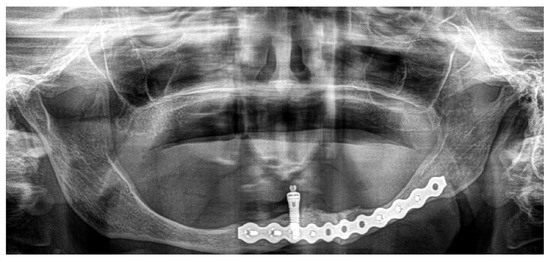

3.2. Case 2